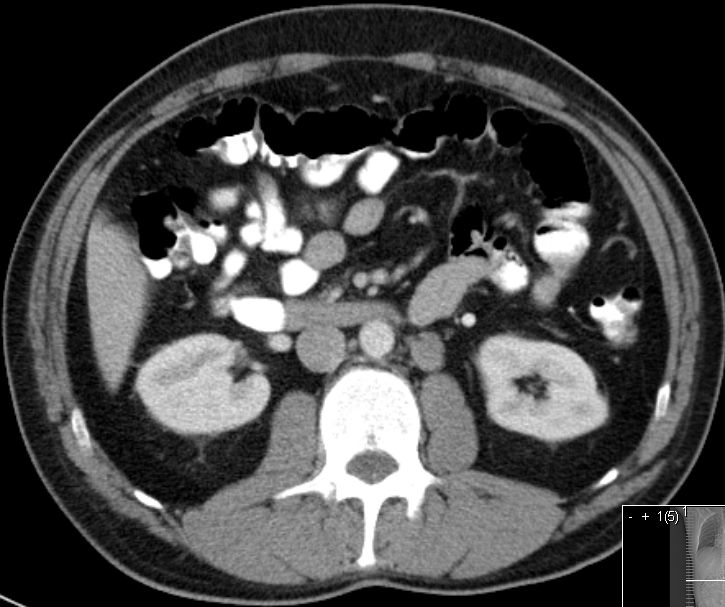

21mm große Lymphknotenmetastase links paraaortal unterhalb des Nierenstiels.![]() |

30-jähriger Mann mit einem 17mm großen reinen Seminom links.

Links paraaortal unterhalb des Nierenstils 3 bis 30mm große Lymphknotenmetastasen![]() | ||